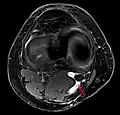

Als Baker-Zyste wurde ursprünglich die Poplitealzyste (popliteal: zur Kniekehle gehörig) des Rheumatikers bezeichnet. Heute wird der Begriff jedoch meist als Synonym für alle poplitealen Zysten, egal welcher Genese, verwendet. Es ist eine Ausstülpung der dorsalen Gelenkkapsel am Kniegelenk zwischen dem Musculus gastrocnemius (medialer Kopf) und dem Musculus semimembranosus. Sie entsteht meist im Zusammenhang mit einem Schaden innerhalb des Kniegelenks, beispielsweise bei einer Läsion des medialen Meniskus, einer arthrotischen Knorpelveränderung oder auch einer rheumatoiden Arthritis. Durch chronische Entzündungsvorgänge kommt es zu einer vermehrten Produktion von Gelenkflüssigkeit, wodurch ein Überdruck im Kniegelenk entsteht. Die Gelenkkapsel gibt dann am Ort des geringsten Widerstands (Locus minoris resistentiae) an o. g. Stelle nach und bildet eine Zyste aus.

Die Diagnose wird neben der klinisch-manuellen Untersuchung durch Ultraschall (Sonographie) und evtl. eine Kernspintomographie erhärtet; dabei werden auch Differentialdiagnosen wie Aneurysmen der Popliteal-Arterie oder -vene[3] ausgeschlossen.